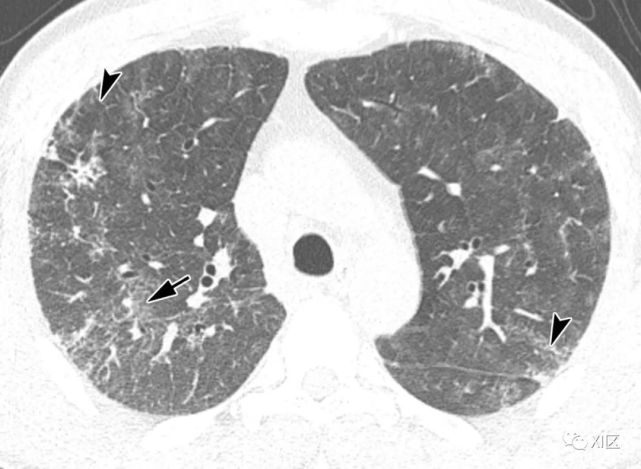

图13 63岁的男子,原发性中枢神经系统淋巴瘤化疗后合并发热,诊断为人博卡病毒肺炎

(上)胸部X线片显示两肺均弥漫性不规则斑块状实变(箭)和GGO。在同一天获得的轴位薄层(1mm)胸部CT图像显示,沿着支气管血管束和肺部周边区域出现不规则的斑块状实变(箭),支气管壁增厚,小叶间隔增厚 (箭头),伴有少量双侧胸腔积液(*)。

Koo H J , Lim S , Choe J , et al. Radiographic and CT Features of Viral Pneumonia[J]. Radiographics, 2018, 38(3):719-739.